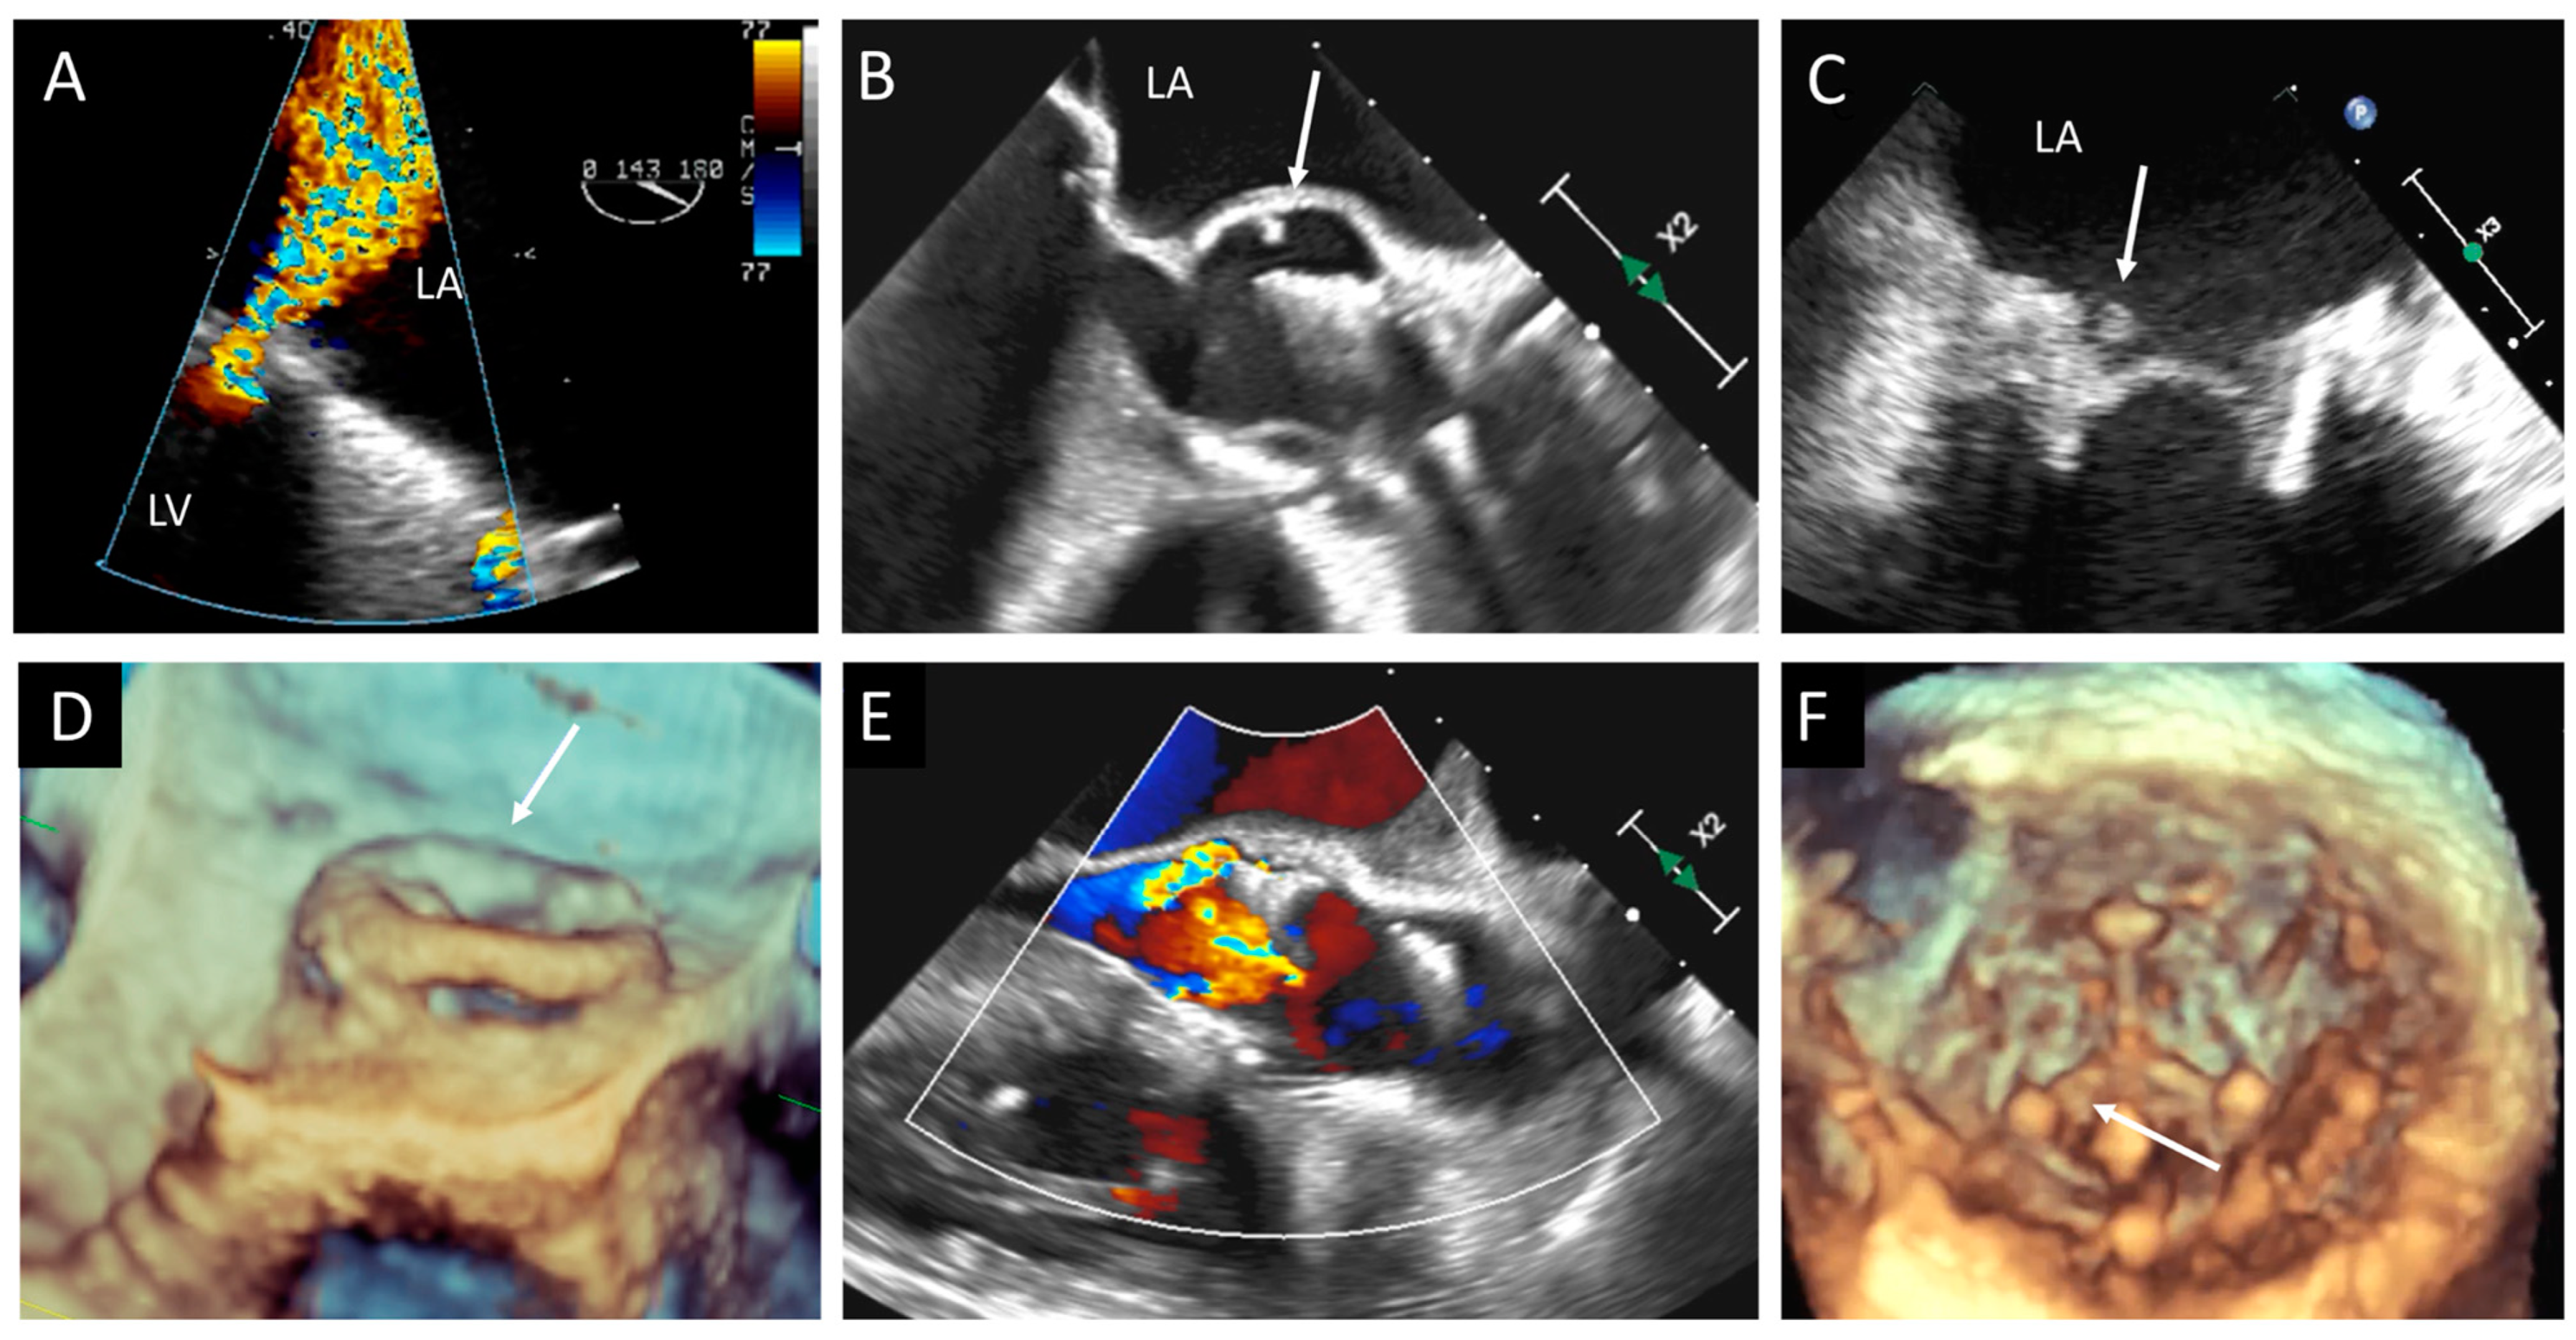

| TTE, TEE | Leaflet and/or ring thickening with diffuse or focal hyperechogenicity (calcifications). Reduced leaflet mobility. Leaflets’ fenestration, avulsion, or perforation. Stenosis or regurgitation. | Iso-hypoechogenic mass adherent to leaflets and ring, with leaflet thickening. Normal or reduced cusp mobility. More often, stenosis; regurgitation is uncommon. | Vegetations, diffuse or focal leaflets thickening, cusps perforation, wear or tear or cusp avulsion. Vegetation motion independent to cusps motion. Paravalvular complications: abscess, pseudo-aneurysm, fistula or dehiscence (and in some cases valve rocking) |

| CCT | Pannus (hypodense): HU ≥ 145; semicircular or circular structure located along leaflets’ surface or stent. Hyperdense leaflet thickening with or without calcifications, along with or without reduced mobility. | No calcifications. HU < 145. Hypoattenuated leaflet thickening (HALT), affecting (HAM) or reducing (RLM) leaflet motion. In some cases, large hypoattenuated mass. | Hypoattenuated mass adherent to leaflets or stent. Paravalvular complications: abscess, pseudo-aneurysm, fistula, or dehiscence. |